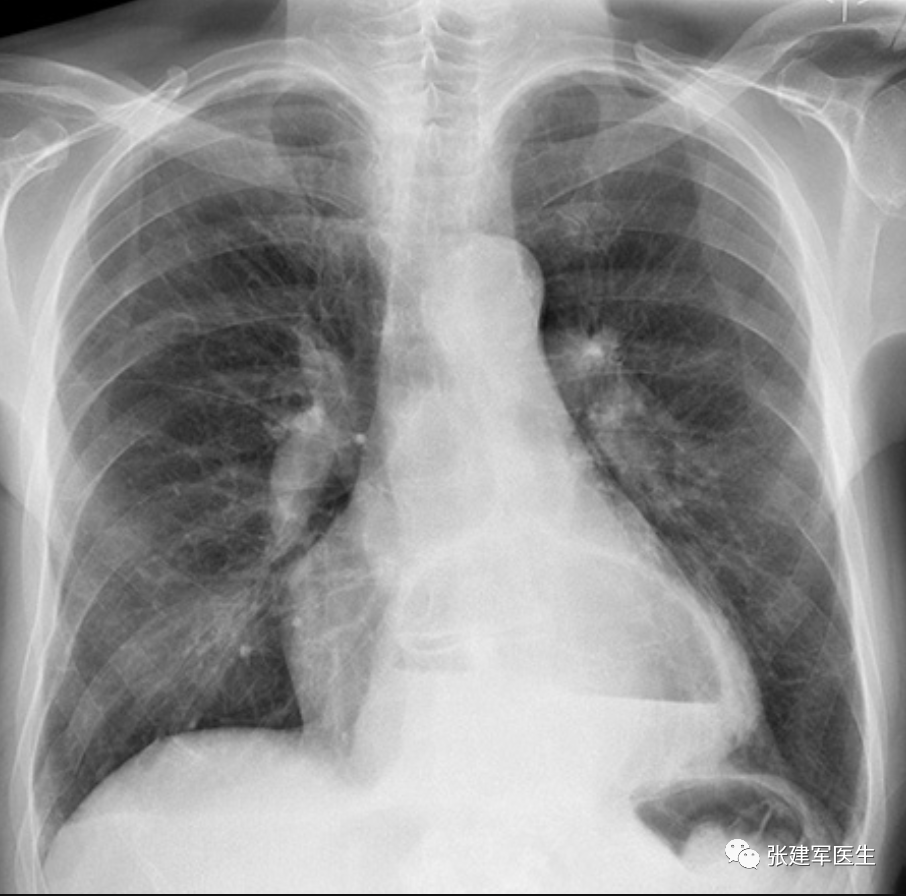

胸部 X 光检查(胸片)

胸部 X 光检查胸部可见不透明软组织影,其内可见液气平面,心脏后方的液气平面是食管旁疝特有的征象。